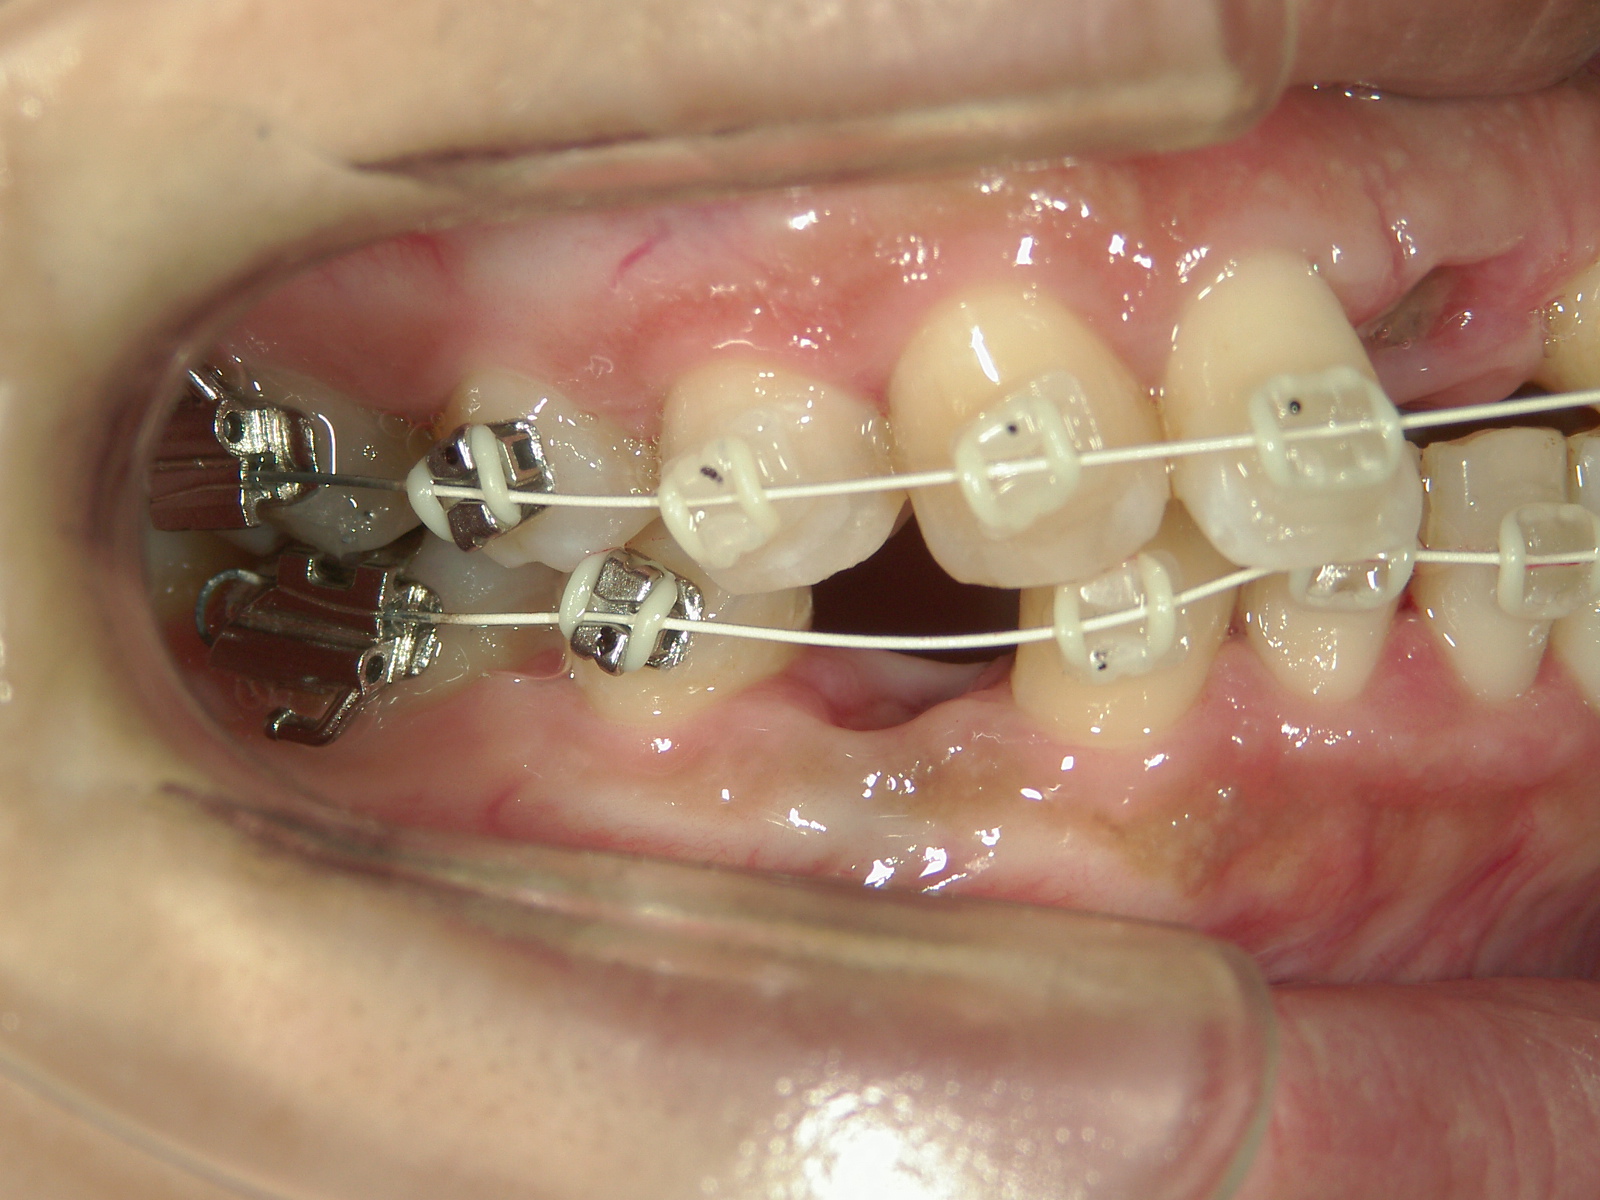

・抜歯した右上前歯の隣りの歯を抜歯してあいたスペースで移動。

・右上犬歯を移動して、開いたスペースへ移動。

・右上 第一小臼歯を移動して犬歯のスペースへ移動。